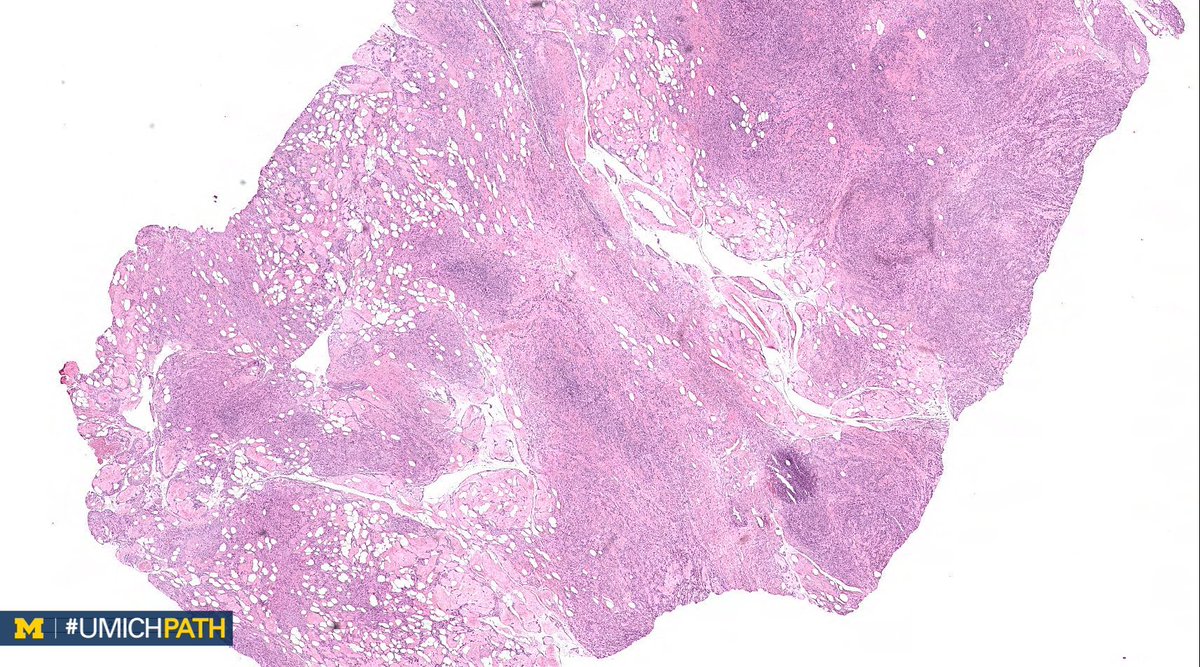

🔬#GYNPath, Day 2 ➡️What’s your #DailyDx of this uterine mass? ➡️We’ll tweet the answer, some quick facts, and the next case tomorrow! #UMichPath

➡️What’s your #DailyDx of this uterine mass?

➡️We’ll tweet the answer, some quick facts, and the next case tomorrow! #UMichPath

A: Uterine tumors resembling ovarian sex cord tumors (UTROSCT). A rare mesenchymal tumor with epithelial-like cells resembling ovarian sex cord tumors. IHC: Sex cord markers are specific, but not always positive. CD10 frequently positive. #GYNPath #DailyDx (H/T @Eggmcmullen)

UMichPath's tweet image. A: Uterine tumors resembling ovarian sex cord tumors (UTROSCT). A rare mesenchymal tumor with epithelial-like cells resembling ovarian sex cord tumors. IHC: Sex cord markers are specific, but not always positive. CD10 frequently positive. #GYNPath #DailyDx (H/T